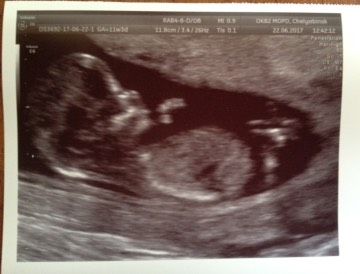

Ну вот и наши 12 неделек, чувствую себя отлично, токсикоза нет, растем, до этого куча страху и переживаний… Поход по врачам, акулист- здорова, лор — здорова, остался стоматолог боюсь но надо… Узи 30 мая гематома 24/10, шок..!!! Сдала анализы на гемостаз оказался повышен РФМК и фибриноген, на консультации гемастазиолог ставит диагноз тромбофлебит и назначает Клексан 20 уколов для разжижения крови..! И пересдача на разные генетические антитела… В понедельник снова к нему..!!! И вот сегодня скрининг… Девочки я самая счастливая, плавает, машет ручками, сердечко бьется..!!! Все показатели в норме, гемотома рассосалась, угрозы больше нет.!!! Есть предлежание но это уже не так страшно..!!! Пол пока рано смотреть но кнопа в порядке… Плакала но от счастья… Дай нам всем Бог того что мы так хотим..!!! Спасибо всем за поддержку ???????? мы счастливы ????????